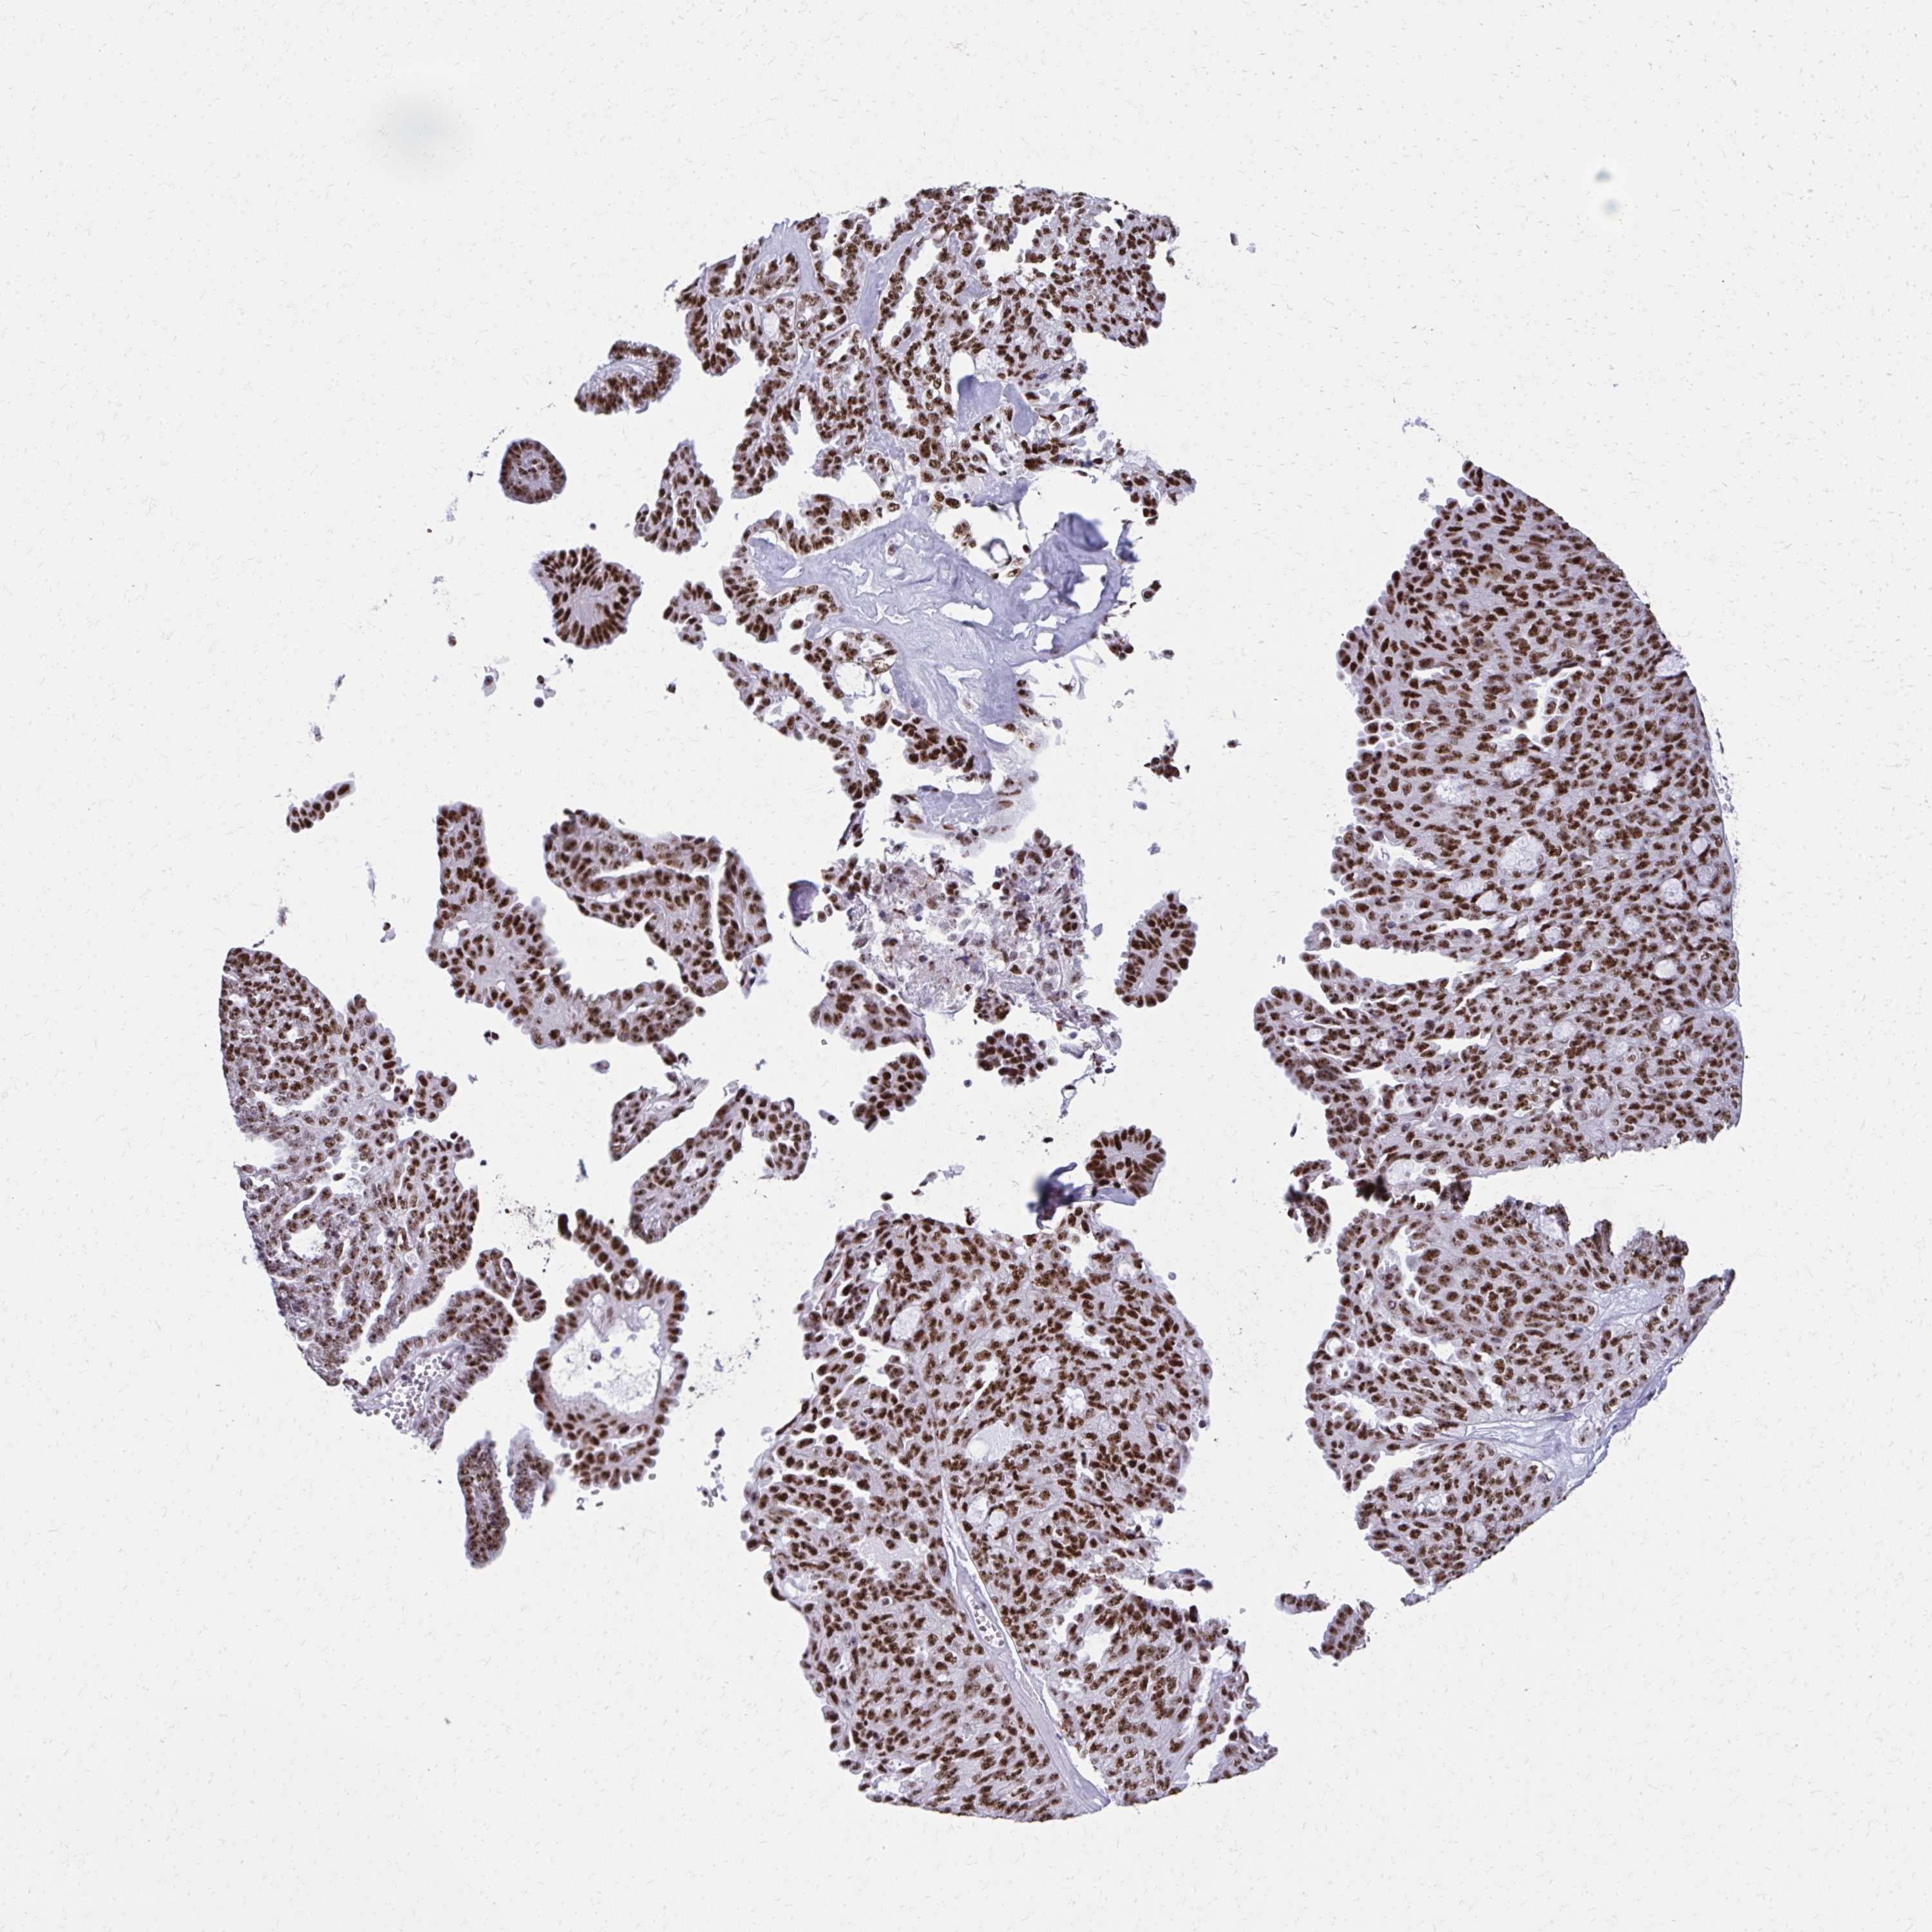

OVARIAN CANCER - Protein expressioni

A mouse-over function shows sample information and annotation data. Click on an image to view it in a full screen mode. Samples can be filtered based on level of antibody staining by selecting one or several of the following categories: high, medium, low and not detected. The assay and annotation is described here.

Note that samples used for immunohistochemistry by the Human Protein Atlas do not correspond to samples in the TCGA dataset.

Antibody stainingi

Antibody staining in the annotated cell types in the current human tissue is reported as not detected, low, medium, or high, based on conventional immunohistochemistry profiling in selected tissues. This score is based on the combination of the staining intensity and fraction of stained cells.

Each image is clickable and will lead to virtual microscopy that enables deeper exploration of all samples and also displays staining intensity scores, fraction scores and subcellular localization as well as patient and tissue information for each sample.

Antibody HPA060760

Staining

High

Medium

Low

Not detected

Intensity

Strong

Moderate

Weak

Negative

Quantity

>75%

75%-25%

<25%

None

Location

Nuclear

Cytoplasmic/membranous

Cytoplasmic/membranous,nuclear

Cystadenocarcinoma, serous, NOS

Cystadenocarcinoma, mucinous, NOS

Carcinoma, endometroid